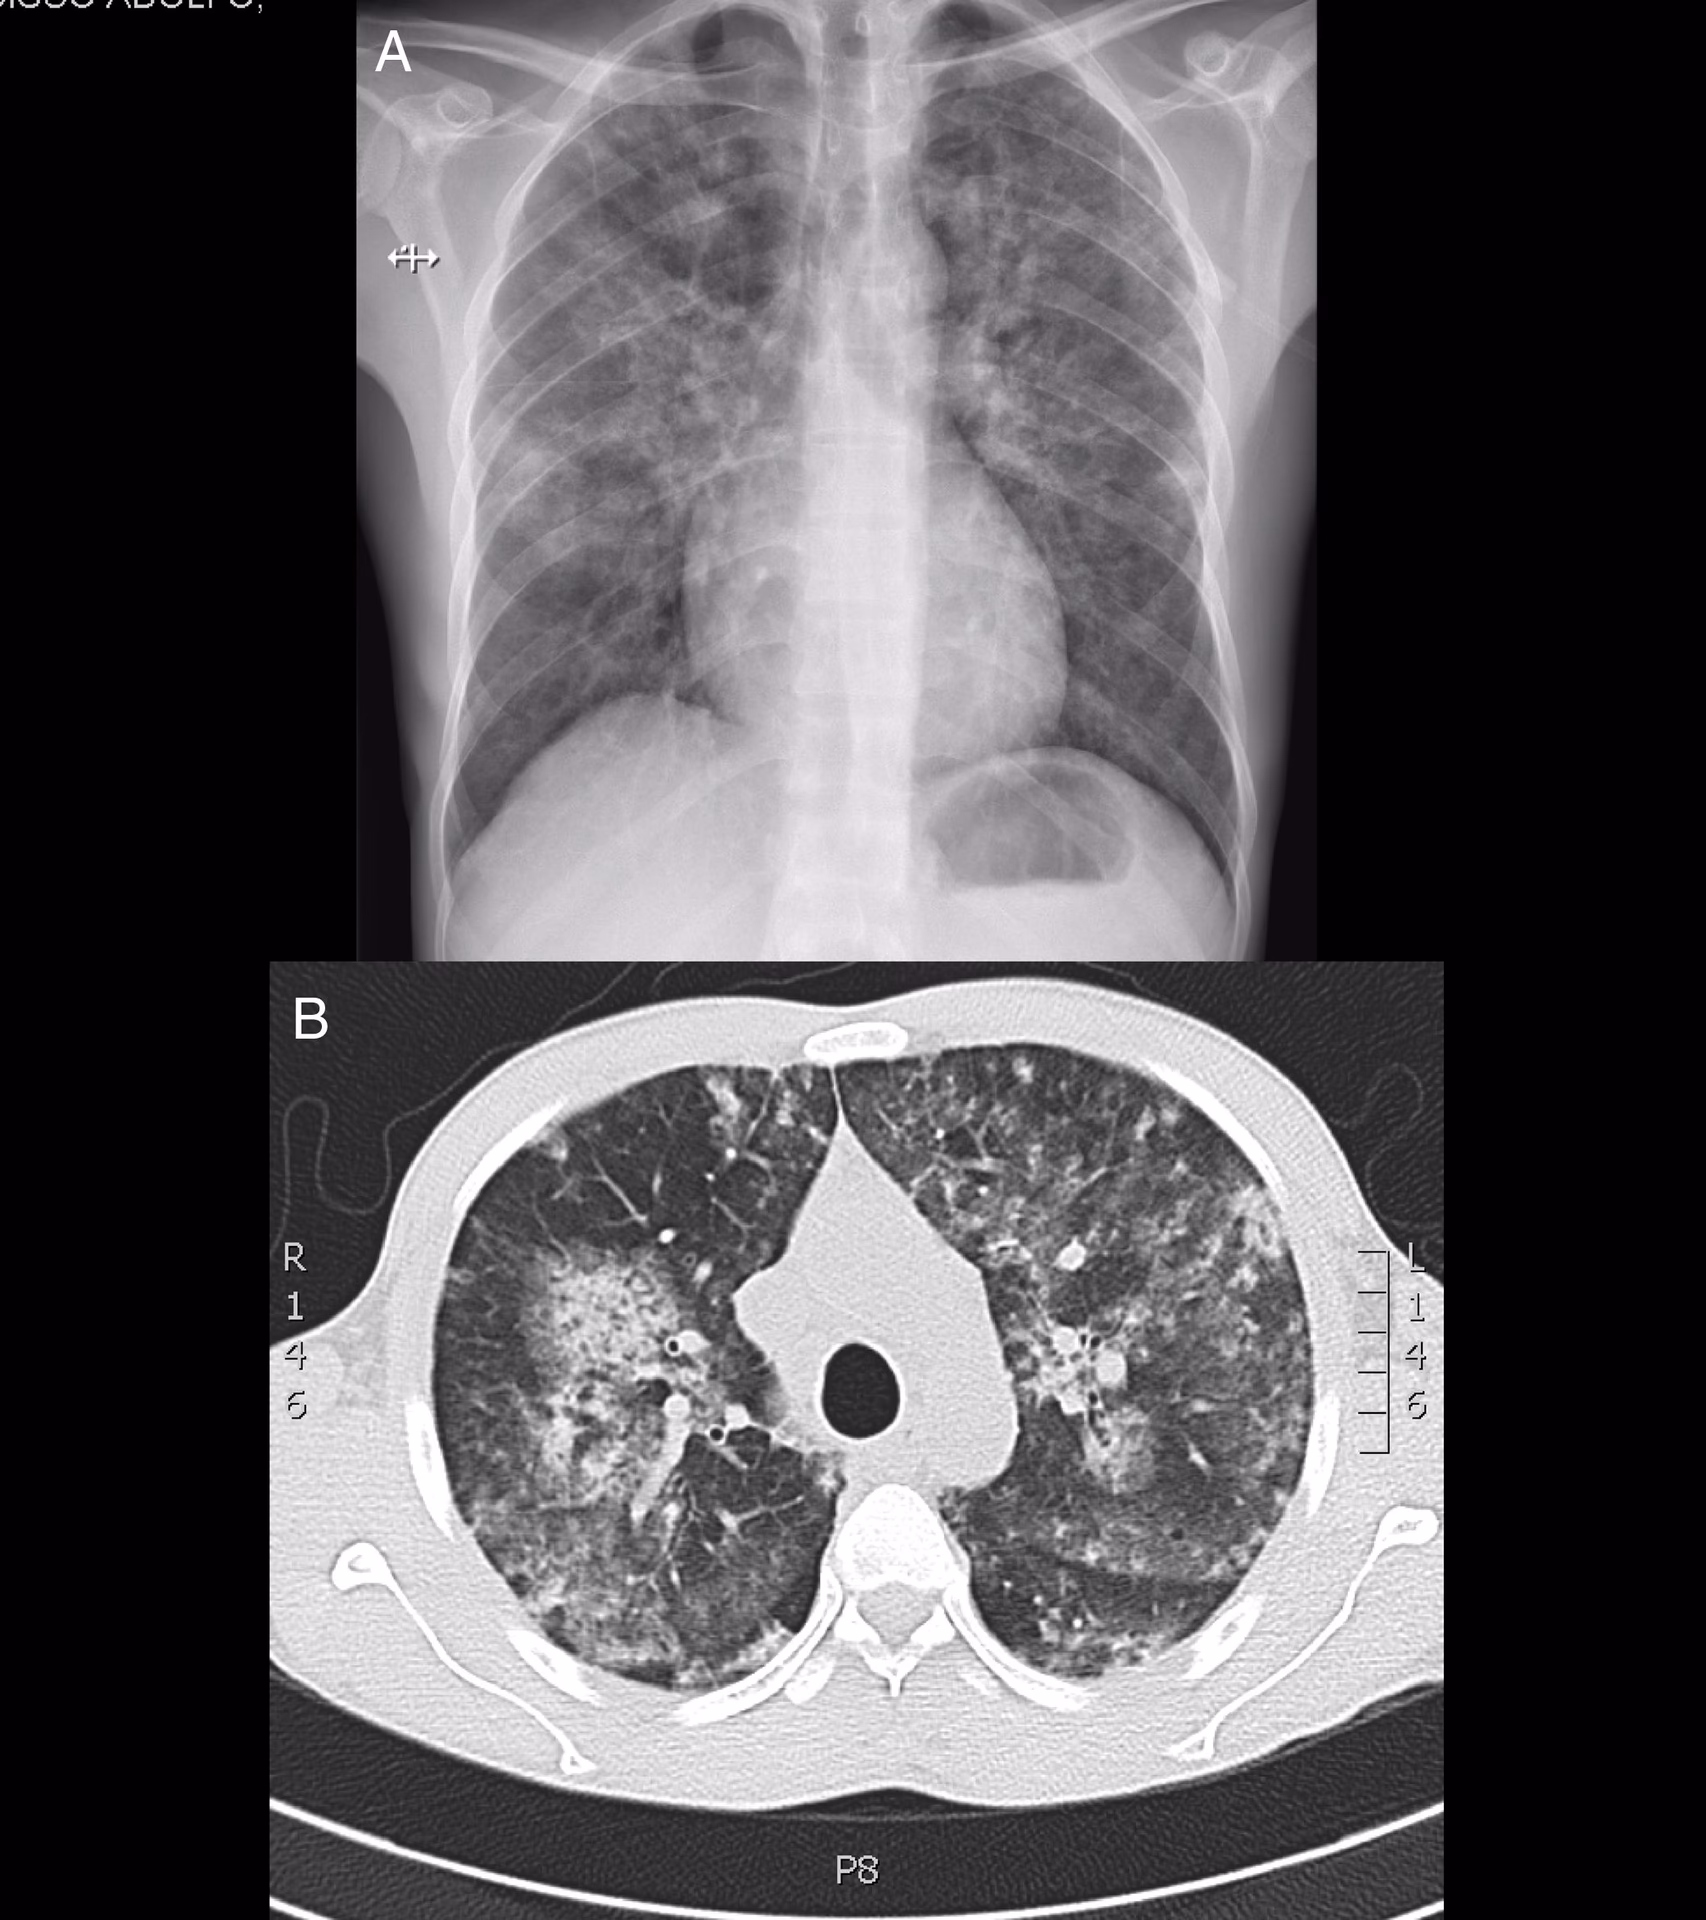

Este ataque autoinmune puede desencadenar una condición llamada vasculitis inducida por levamisol, que es la inflamación de los vasos sanguíneos. Es esta inflamación la que causa las terribles lesiones cutáneas necróticas, al cortar el suministro de sangre a la piel. Además, se han reportado otros efectos colaterales graves, como la aparición de bullas hemorrágicas, que son grandes ampollas llenas de sangre, indicativas de un daño vascular severo. A largo plazo, esta vasculitis puede afectar a órganos internos como los riñones, los pulmones y las articulaciones, provocando un daño sistémico irreversible.